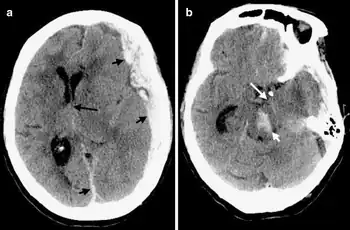

Duret haemorrhages can be demonstrated by medical imaging techniques of CT or MRI though difficult.[9]